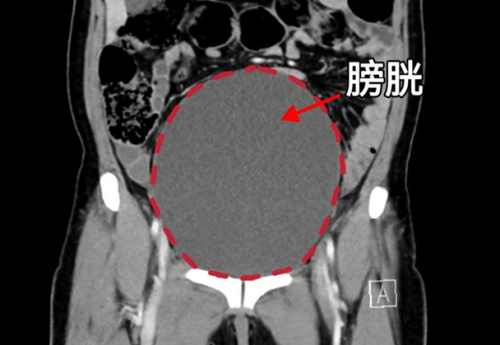

(南华大学附属长沙中心医院)。检查发现,其子宫脱垂已导致尿道完全梗阻,膀胱高度膨胀,且脱垂组织因长期摩擦导致严重溃烂、感染,病情危急。

CT显示膀胱高度膨胀、尿道梗阻